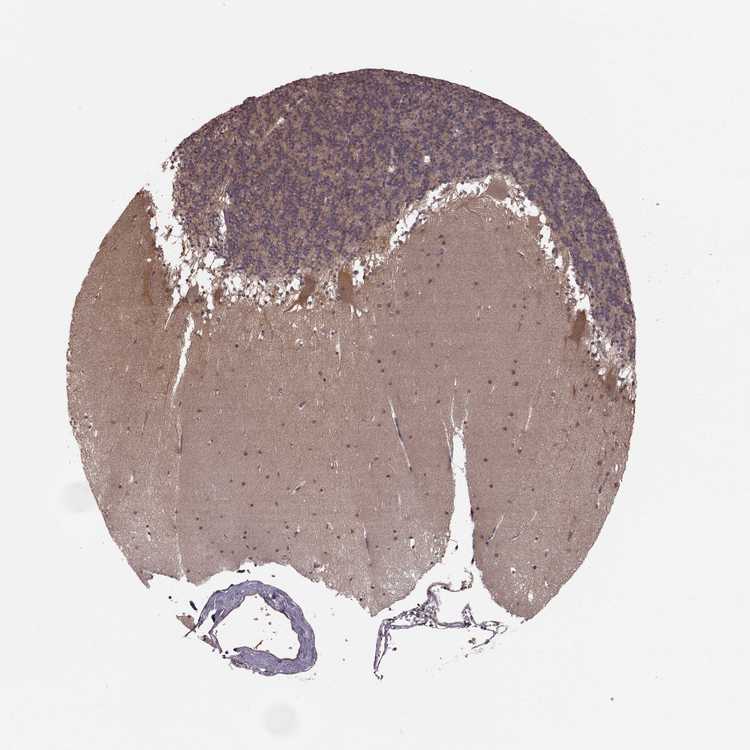

CEREBELLUM - Antibody stainingi

Antibody staining in the annotated cell types in the current human tissue is reported as not detected, low, medium, or high, based on conventional immunohistochemistry profiling in selected tissues. This score is based on the combination of the staining intensity and fraction of stained cells.

Each image is clickable and will lead to virtual microscopy that enables deeper exploration of all samples and also displays staining intensity scores, fraction scores and subcellular localization as well as patient and tissue information for each sample.

Antibody HPA054508Antibody HPA059315

Purkinje cells MediumNot detected

Cells in granular layer LowNot detected

Cells in molecular layer LowLow